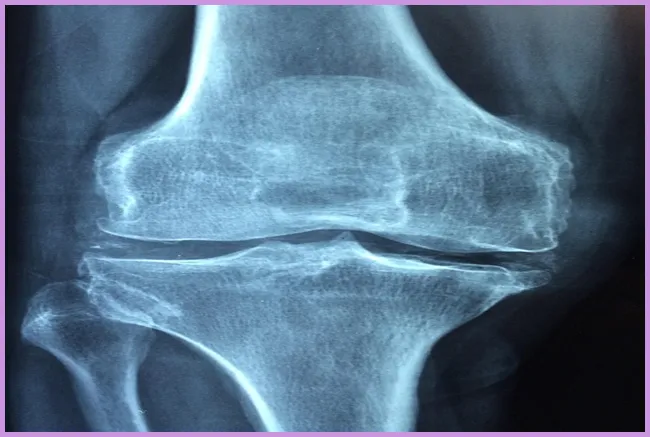

관절 문제, 특히 슬관절의 이상은 허벅지 통증을 유발할 수 있습니다. 관절염 혹은 관절의 퇴행성 변화가 이러한 통증의 주요 원인으로 작용합니다. 무릎 관절에 문제가 생기면 통증이 허벅지로 방사되는 경우가 많습니다.

관절 문제가 의심되는 경우, 통증뿐만 아니라 관절의 경직, 부종 등을 동반할 수 있습니다. 이러한 증상을 느낀다면 검사를 통해 상태를 확인해야 합니다.